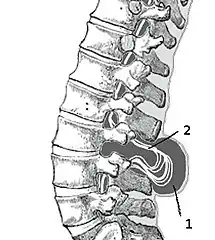

X-ray computed tomography scan of unfused arch at C1 Myelomeningocele in the lumbar area

Myelomeningocele in the lumbar area

(1) External sac with cerebrospinal fluid

(2) Spinal cord wedged between the vertebrae